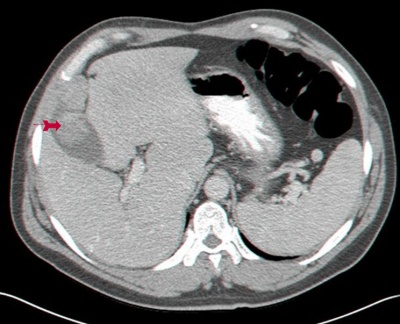

או טומוגרפיה ממוחשבת. CT בטן יכול להדגים את השאת בכיס המרה (תצלום 47.8) באם היא פורצת לכבד (תצלום 48.8) או מערבת בלוטות (רגישות נמוכה).